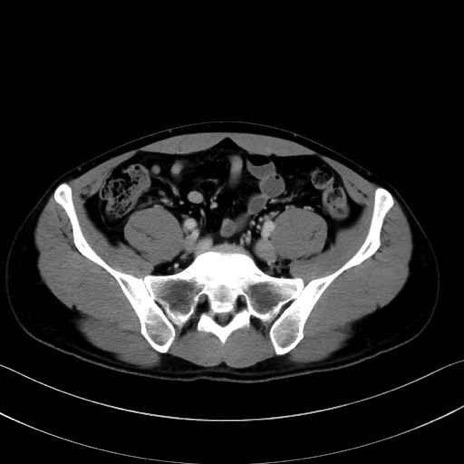

小殿筋 (Gluteus minimus)